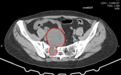

入院后进一步检查发现,郭女士盆腔内的肿瘤确诊为骶骨前神经鞘瘤,大小约8.6*6.5*8cm(前后径*左右径*上下径)。据了解,患者在6年前就发现腹部有一包块,但未引起重视,没有进行治疗,这才引起了更大的健康隐患。

想要拿掉肿瘤可不简单,肿瘤从骶孔穿过,且已经和盆腔内的直肠、子宫争夺“地盘”。巨大的神经鞘瘤将周围的神经紧密包裹,骶孔内的神经也深陷肿瘤内,整个肿瘤更像一个“大葫芦”占据盆腔内,如果任其发展,将会导致严重的后果,必须尽快手术摘除。